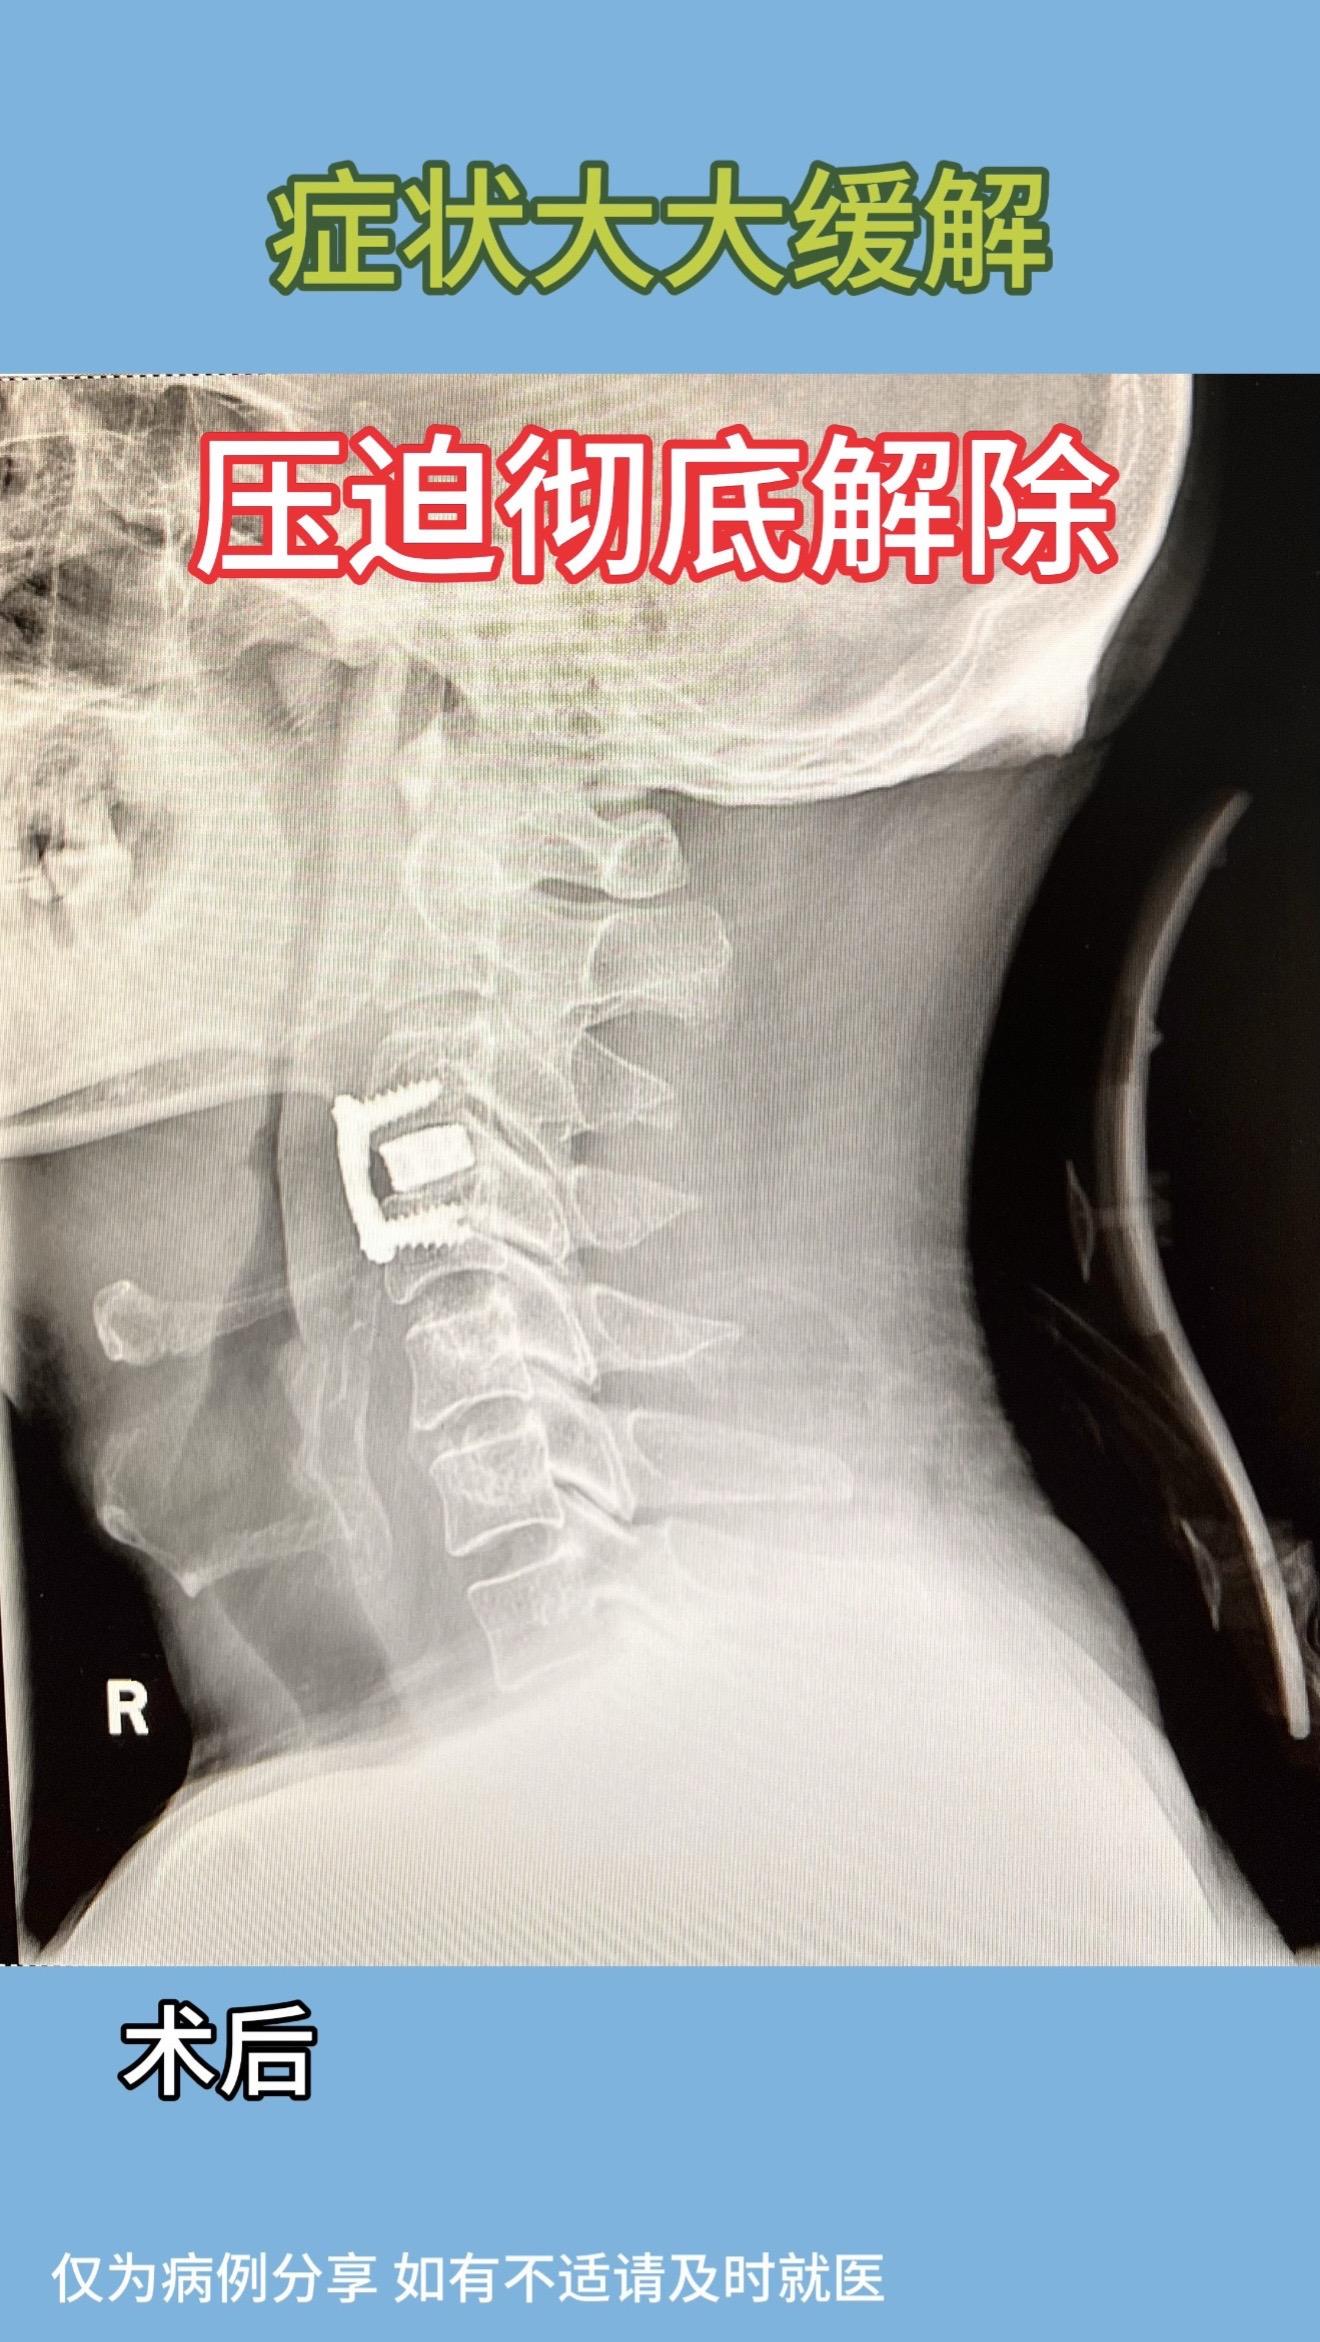

40多岁男性,右手无力、肌肉萎缩半年,右手持筷不能,只能用勺子吃饭。左手无力,症状较右侧稍轻。磁共振示高位颈3/4突出,脊髓信号改变。术后症状大大缓解,术后磁共振示压迫解除彻底。